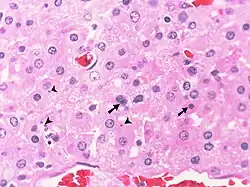

La malakoplakia, una afección a menudo asociada con la inmunodeficiencia y caracterizada por una función anormal de los macrófagos, consiste en láminas de histiocitos grandes en respuesta a una infección bacteriana. Representa una respuesta inflamatoria relativamente ineficaz debido a la persistencia de bacterias y/o productos de degradación bacteriana dentro de los histiocitos. En los pulmones casi siempre es causada por una infección por Rhodococcus equi, pero puede ser causada por otras bacterias. La malakoplakia es morfológicamente muy similar a la infección por el complejo Mycobacterium avium en pacientes con SIDA y a la enfermedad de Whipples y la lepra lepromatosa. La característica distintiva y diagnóstica de la malacoplasia es la presencia de pequeñas estructuras intracelulares calcificadas concéntricamente llamadas cuerpos de Michaelis-Gutman (cuerpos MG). Los cuerpos de MG también contienen hierro teñible. También pueden estar presentes calcificaciones intracitoplasmáticas que no tienen la apariencia típica de los cuerpos de MG. Las flechas indican los cuerpos típicos de Michaelis-Gutman (cuerpos MG) con una apariencia de "ojo de buey". Las puntas de flecha apuntan a calcificaciones intracelulares que no son cuerpos de MG pero que probablemente estén relacionadas con ellos.